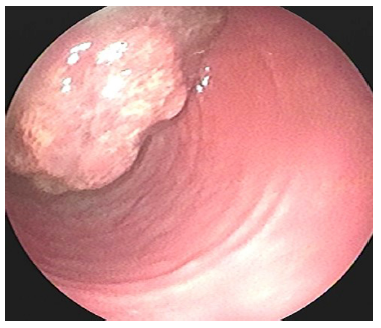

Se trata de una mujer de 58 años de edad quien consultó por un cuadro de pérdida anormal de peso de 6 kg en el último semestre, asociado con hematoquecia escasa y deposiciones diarreicas ocasionales, sin antecedentes patológicos, con antecedente familiar de cáncer de colon (hermana durante la quinta década de la vida). Se realizó una colonoscopia total que demostró tres pólipos: uno en el colon ascendente de 7 mm (biopsia: adenoma velloso con displasia de bajo grado) (Figura 1), un pólipo sésil de 50 mm en ángulo hepático (biopsia: adenoma velloso con displasia de bajo grado) (Figura 2) y un pólipo de 30 mm en el recto superior (biopsia: adenoma con displasia de bajo grado) (Figura 3); el hemograma resultó normal en las 3 líneas celulares. Se llevó a polipectomía endoscópica de pólipo rectal tipo piece meal con asa caliente, cuyo estudio histopatológico reportó adenoma tubulovelloso con displasia de bajo grado.